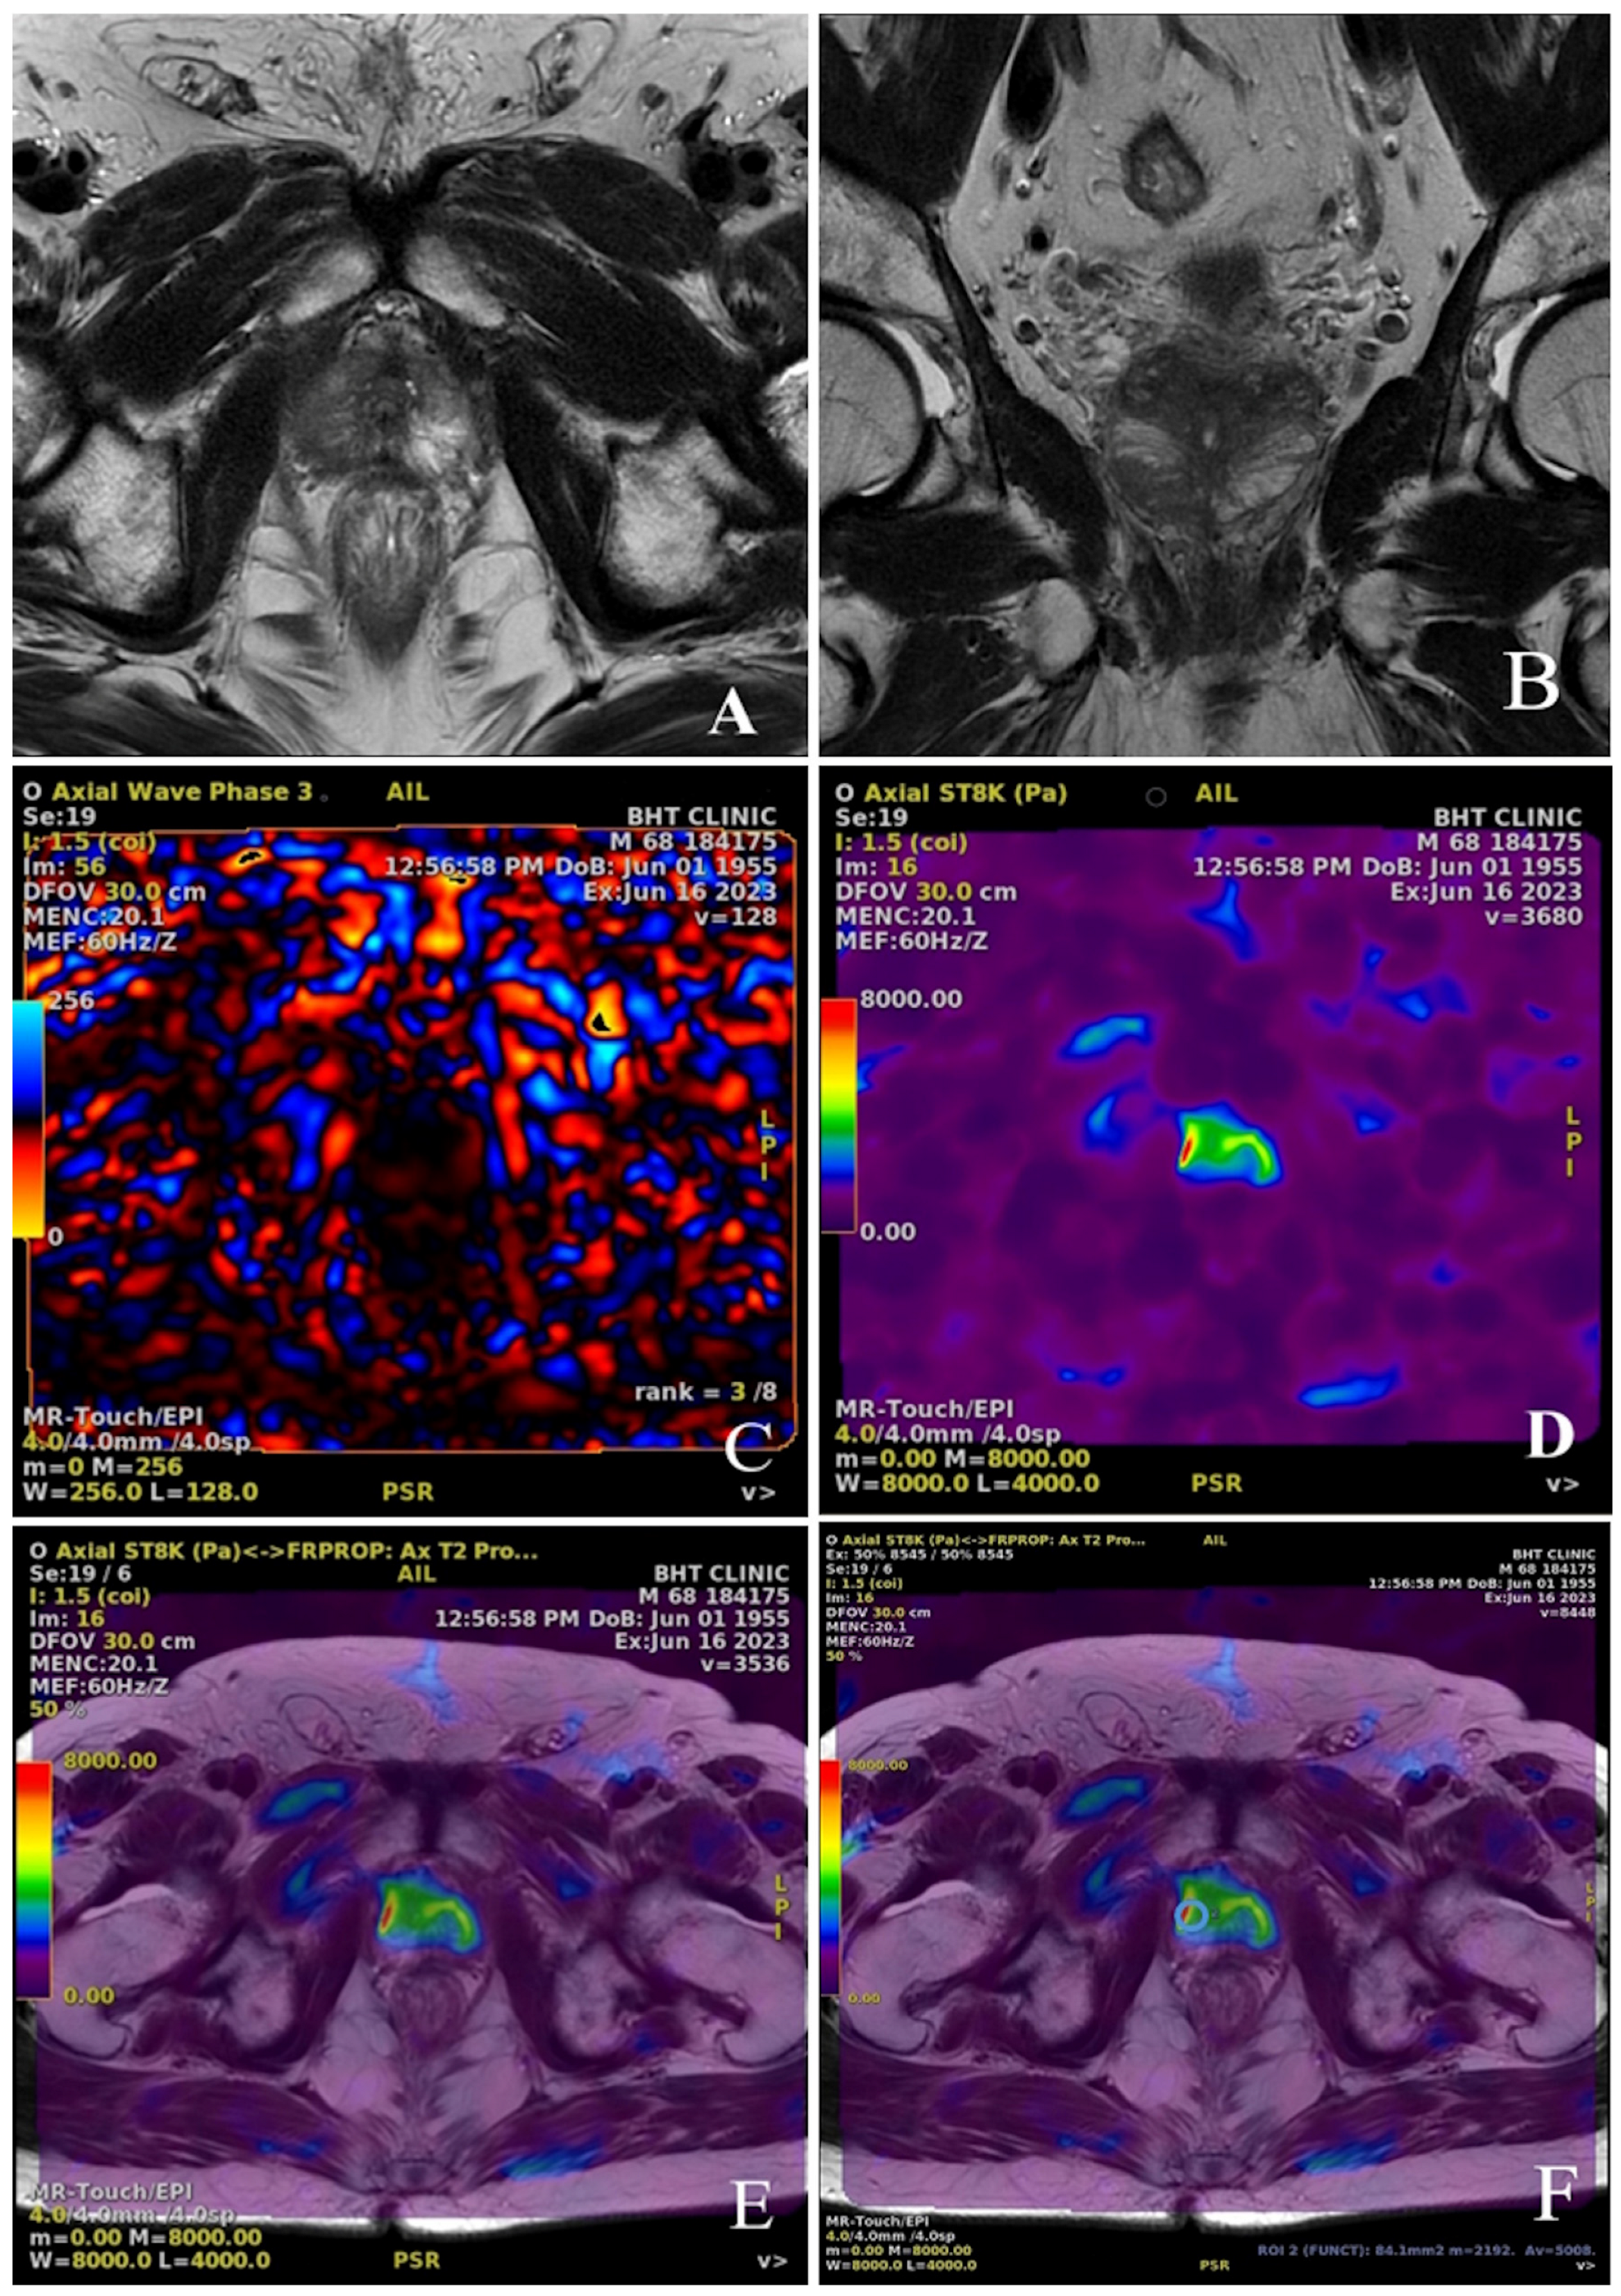

1. Introduction

2. Materials and Methods

2.2. Study Protocol

2.4. Radiological Measurements